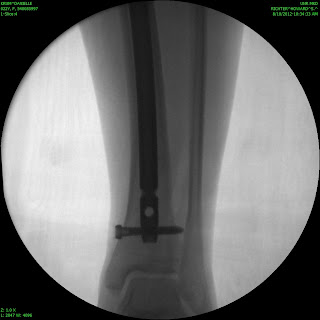

Sorry that I have been MIA for so long! I actually broke my leg on August 9th… I fractured my tibia (the big weight bearing bone in your shin) all the way through. I had the option to be in a full length cast (from my hip to my toes) for 8 weeks, or to have surgery and a rod placed so that I can walk on my leg. I chose to have surgery and now I am just going through recovery. I am working on teaching myself how to walk normal with that leg again. I am happy to be up and moving and not in a cast, but its definitely not a fun process. I have new crafts to put up soon! Some darling candy corns and a pumpkin set for the porch! I will work on getting those posted as soon as I can.

Here are some awesome pictures of my broken leg!